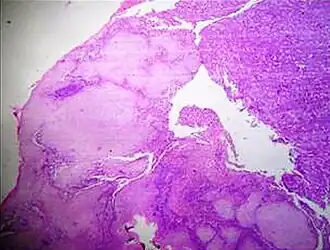

A crush artifact is an artificial elongation and distortion seen in histopathology and cytopathology studies, presumably because of iatrogenic compression of tissues. Distortion can be caused by the slightest compression of tissue and can provide difficulties in diagnosis.[2][3] It may cause chromatin to be squeezed out of nuclei.[4] Inflammatory and tumor cells are most susceptible to crush artifacts.[4]

-

Cellulose contamination, in H&E stain and polarized light -

Cardiac muscle (bottom) with contamination from thyroid tissue (center) -

Crush artifact from compression by forceps on the tissue sample -

Folding artifacts (white arrows) and a crush artifact (black arrow, with cytoplasmic hypereosinophilia and nuclear pleomorphism) from a needle -